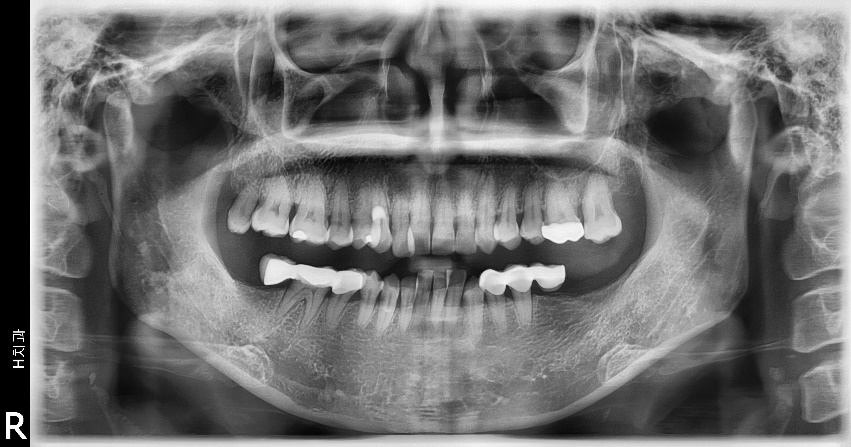

마무리된 교합은 초진시에 동일하게 양측 Class 1 교합으로 마무리하였으며 측모두 부방사선 사진에서 보듯 교정중 발생했던 전치의 flare가 개선되었습니다.

구치부 상실시 임플란트 조기식립은 고정원 확립에 있어 상당한 장점을 가지고 있으므로 대합치와 인접치의 최종위치를 예상해 정확한 위치에 식립될 경우 교정치료에 유용하게 이용할 수 있다고 생각됩니다.

최종적으로 대합치의 상태를 보고-특히 교정을 먼저한 경우는 원래의 해부학적위 치와 달라지는 경우가 있을 수 있기 때문에 이러한 여러요소들을 고려해서 임플란트식립과 보철을 마무리하는 것이 좋습니다. 위의 증례에서는 이종골과 흡수성막을 통한 수평골확장술을 시행하며 4.5와 5.0직경의 8mm임플란트로 마무리하였습니다.